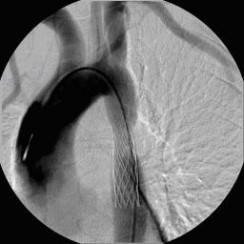

Aortenkoarktationsstenose nach Stentimplantation

(Bild 2 von 4)